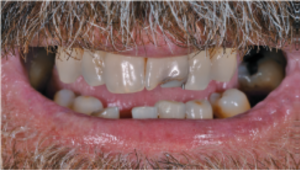

a. Situación clínica inicial del paciente con compromiso periodontal avanzado y movilidad severa de las piezas dentales. Evaluación radiológica previa al tratamiento para el análisis del volumen óseo y la planificación de implantes.

Resultado estético final tras la colocación de la prótesis definitiva, a un paciente con línea de sonrisa alta, sin compromiso visual de los accesos de tornillo. Caso clínico publicado originalmente en la revista científica Dentale Implantologie, Vol. 23, nº 2 (2019).